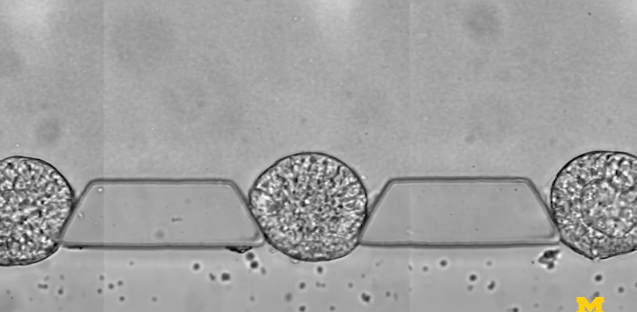

圖 | 微流控芯片的特寫照片,該芯片幫助干細胞組織成胚胎樣結(jié)構(gòu),用于研究早期人類發(fā)育(來源:Fu Lab, Michigan Engineering)

研究人員由此開發(fā)出來一種微流體裝置——由三個通道組成,分別用于放置細胞可嵌入的材料,裝載干細胞,以及輸運刺激干細胞分化的因子,借此研究人員能夠控制干細胞在早期人類胚胎中面向主要細胞譜系的分化,可以可靠地產(chǎn)生數(shù)百或數(shù)千種類似胚胎的結(jié)構(gòu)。

為了模擬胚胎著床后的發(fā)育階段,即羊膜囊開始形成的時候,也是干細胞向分化成組織邁出第一步的時候,研究小組在一個可伸縮的三通道微流體系統(tǒng)中嘗試培育干細胞。中央通道包含一種模擬子宮壁的凝膠,兩側(cè)有一個通道用于為干細胞補充營養(yǎng),另一個通道用于遞送引導。